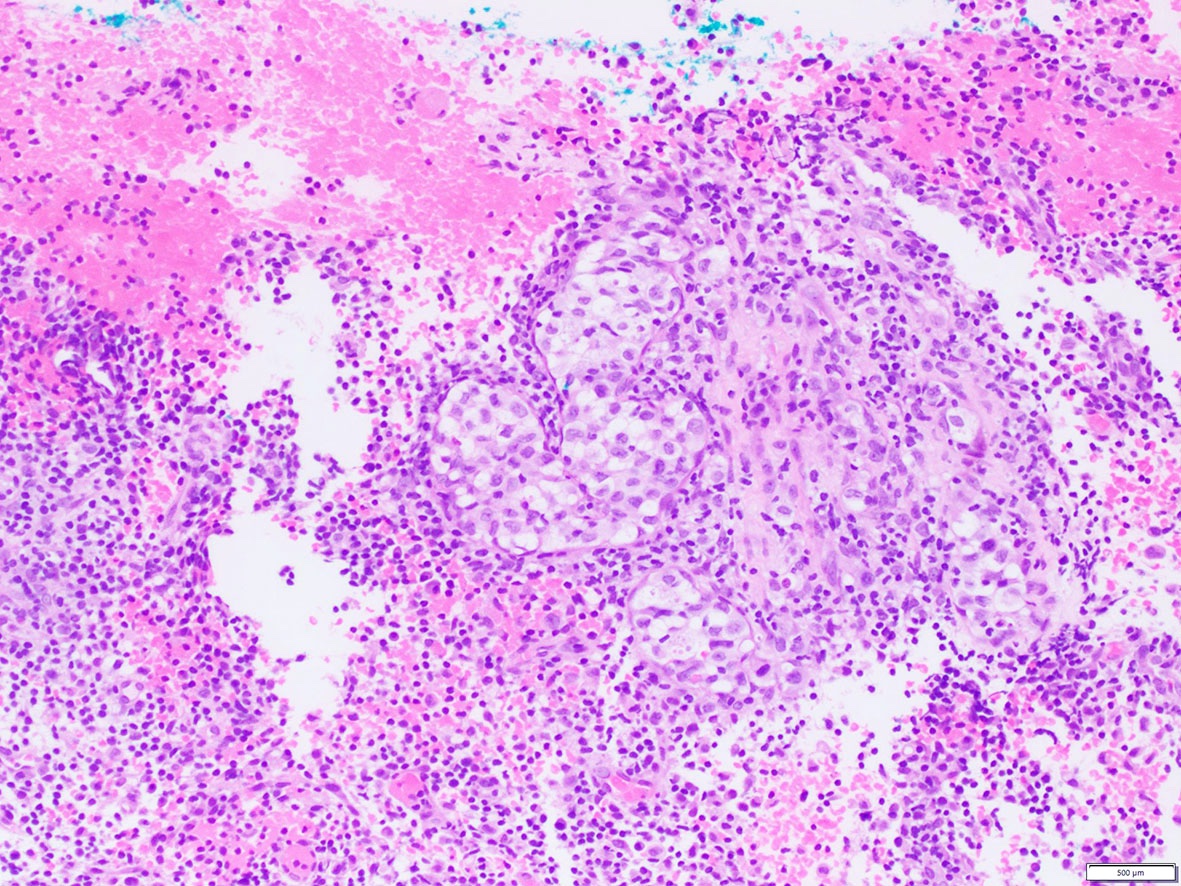

Microscopic (histologic) images

Contributed by A. Cristina Vargas, M.B.B.S., Ph.D., Patricia Guzman, M.D., Fiona Bonar, M.B.B.Ch., Alison Cheah, M.B.B.S. and Martin Jones, M.B.B.S.

Positive staining - disease

- ALK overexpression as a result of gene translocations / fusions:

- ALK+ anaplastic large cell lymphoma (ALCL) (Science 1994;263:1281, Semin Diagn Pathol 2020;37:57)